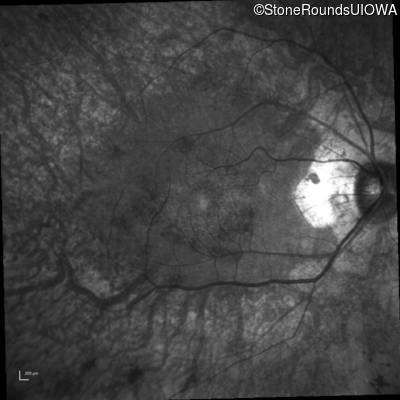

Infrared Fundus Photograph - Right - 20/25 -2 sc

Exemplar